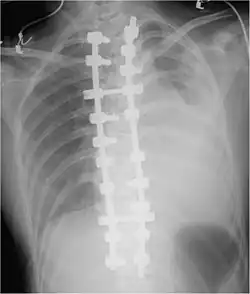

Surgery

About 10–20% of traumatic hemothoraces require surgical management.[6] Larger hemothoraces, or those that continue to bleed following drainage, may require surgery. This surgery may take the form of a traditional open-chest procedure (a thoracotomy), but may be performed using video-associated thoracoscopic surgery (VATS). While there is no universally accepted cutoff for the volume of blood loss required before surgery is indicated, generally accepted indications include more than 1500 mL of blood drained from a thoracostomy, bleeding rate of over 500mL/hr in the first hour followed by over 200 mL, hemodynamic instability, or the need for repeat blood transfusions.[8][6] VATS is less invasive and cheaper than an open thoracotomy, and can reduce the length of hospital stay, but a thoracotomy may be preferred when hypovolemic shock is present,[3] in order to watch bleeding.[34] The procedure should ideally be performed within 72 hours of the injury as delay may increase the risk of complications.[19] In clotted hemothorax, VATS is the generally preferred procedure to remove the clot, and is indicated if the hemothorax fills 1/3 or more of a hemithorax. The ideal time to remove a clot using VATS is at 48–96 hours, but can be attempted up to nine days after the injury.[6]